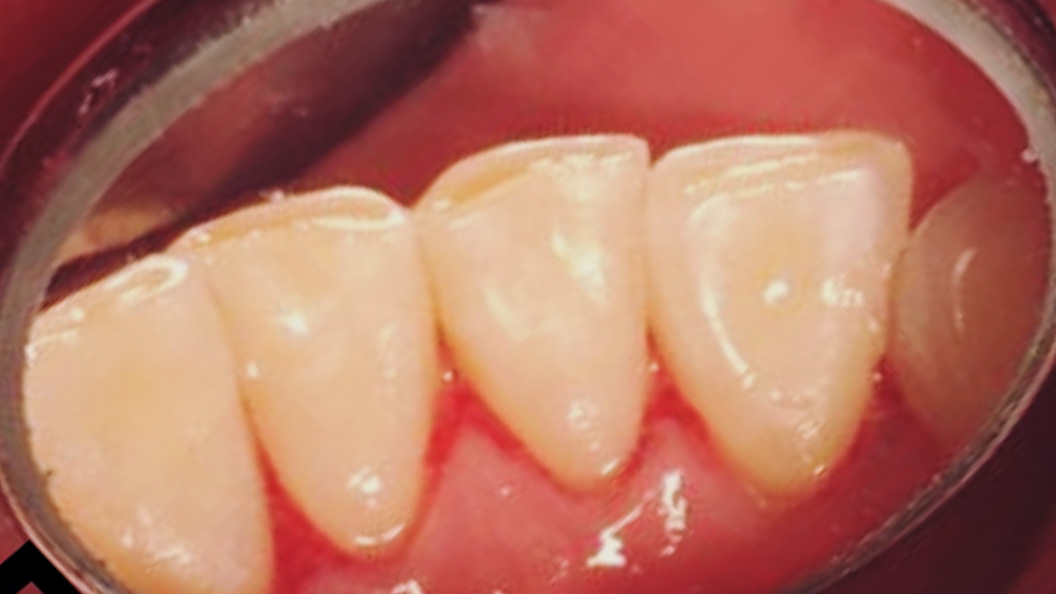

До и после лечения

У пациентки «Стоматологии Комфорта» были жалобы на кровоточивость дёсен во время чистки зубов. Также во время осмотра был обнаружен налёт на поверхности зубов. В результате поставлен диагноз: хронический генерализованный катаральный гингивит.

В процессе лечения были проведены мероприятия:

- проведена профессиональная гигиена полости рта;

- завершающая чистка зубов пастой Detatrine.